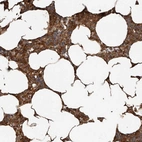

Immunohistochemical staining of human bone marrow shows cytoplasmic positivity in hematopoietic cells.